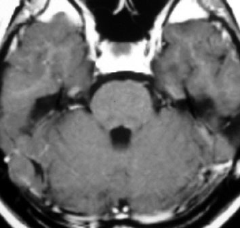

放射線誘発膠芽腫(グリオブラストーマ)

放射線治療10年後です。側脳室の中の腫瘍は小さくなって再発はありませんが,脳幹部と小脳に膠芽腫が発生しました(右側のMRI)。この腫瘍も放射線誘発腫瘍と考えられます。脳幹部の膠芽腫は助かることがない悪性腫瘍です。